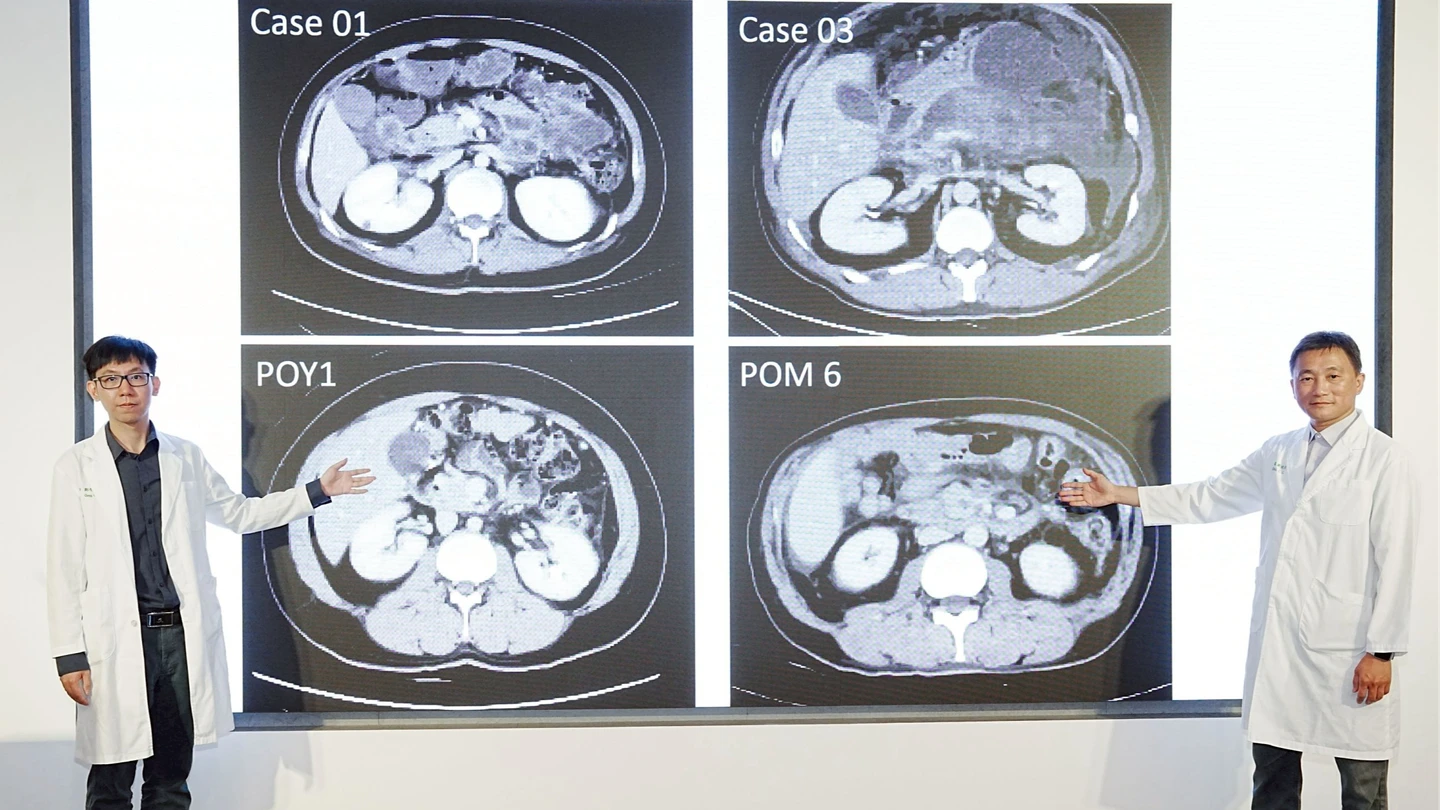

【記者王煌忠/台中報導】一名39歲許姓男子因上腹疼痛持續數日,誤以為只是胃脹氣未加理會,直到症狀惡化才就醫,經診斷竟為膽結石引發的壞死性胰臟炎,所幸在中國醫藥大學附設醫院多專科團隊合作下,採行國際主流「延遲介入、優先微創」四階段整合治療策略,成功控制病情並完成微創手術,許男術後恢復良好,已回歸正常生活。

中醫大附醫一般外科醫師鄭智忠表示,許姓男子過去無胰臟疾病病史,初期僅出現上腹疼痛,未料病情迅速惡化,經檢查確認為膽結石阻塞胰管,引發急性且嚴重的壞死性胰臟炎,屬高風險重症,醫療團隊隨即啟動整合照護機制,由內科、外科及放射診療科跨科合作,分階段進行治療。

院方表示,所謂四階段整合治療,首先在急性期以積極輸液、建立腸道營養及精準止痛為主,穩定患者生命徵象;待病況穩定後,再透過影像導引進行經皮引流,降低感染與內部壓力。接續由消化內科視病灶位置,進行內視鏡透壁引流,並置入金屬支架,以低侵襲方式處理壞死組織;最後再由外科團隊執行影像輔助的後腹腔微創清創手術,以小切口精準移除壞死組織,兼顧安全與療效。

葉俊杰率領的醫療團隊,去年就收治7名重症壞死性胰臟炎患者,平均年齡約52歲,皆屬感染高風險族群。經跨科別採行上述整合治療後,已有5人順利康復出院,其餘2人持續追蹤治療中,整體存活率較傳統治療模式顯著提升。